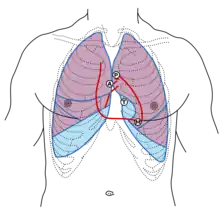

- For the best cardiac examination, it is important to have the patient both sit up and lay down at a 30-45˚ angle. Tapping with the fingertips (also known as percussion) can be used to estimate the size of the heart, though palpation is more accurate.[3] From the left side of the chest, the doctor can tap the spaces between the ribs with the tips of their middle finger to listen for the dullness that will be present over the heart.[1] Listening with a stethoscope (also known as auscultation) to all four areas of the heart: aortic, pulmonic, tricuspid and mitral. Any murmurs, rubs or gallops should be noted. Gallops are also known as a third (S3) or fourth (S4) heart sound. The absence of abnormalities (normal) may be recorded as "no m/r/g". The ACC and the AHA have called cardiac auscultation "the most widely used method of screening for valvular heart disease."[3] Because of its importance to the cardiac examination, cardiac auscultation has been covered in-depth elsewhere.

- A customized pulmonary examination can also help diagnose a cardiac disease, such as in the auscultation of certain lung sounds or pleural effusions (e.g., in the case of heart failure). An unusual sound that comes from the pulmonary examination can point to a disease of the heart. Inspection, palpation, percussion and auscultation of the lungs are all important for the cardiac examination. The specifics of pulmonary examination can be covered elsewhere.